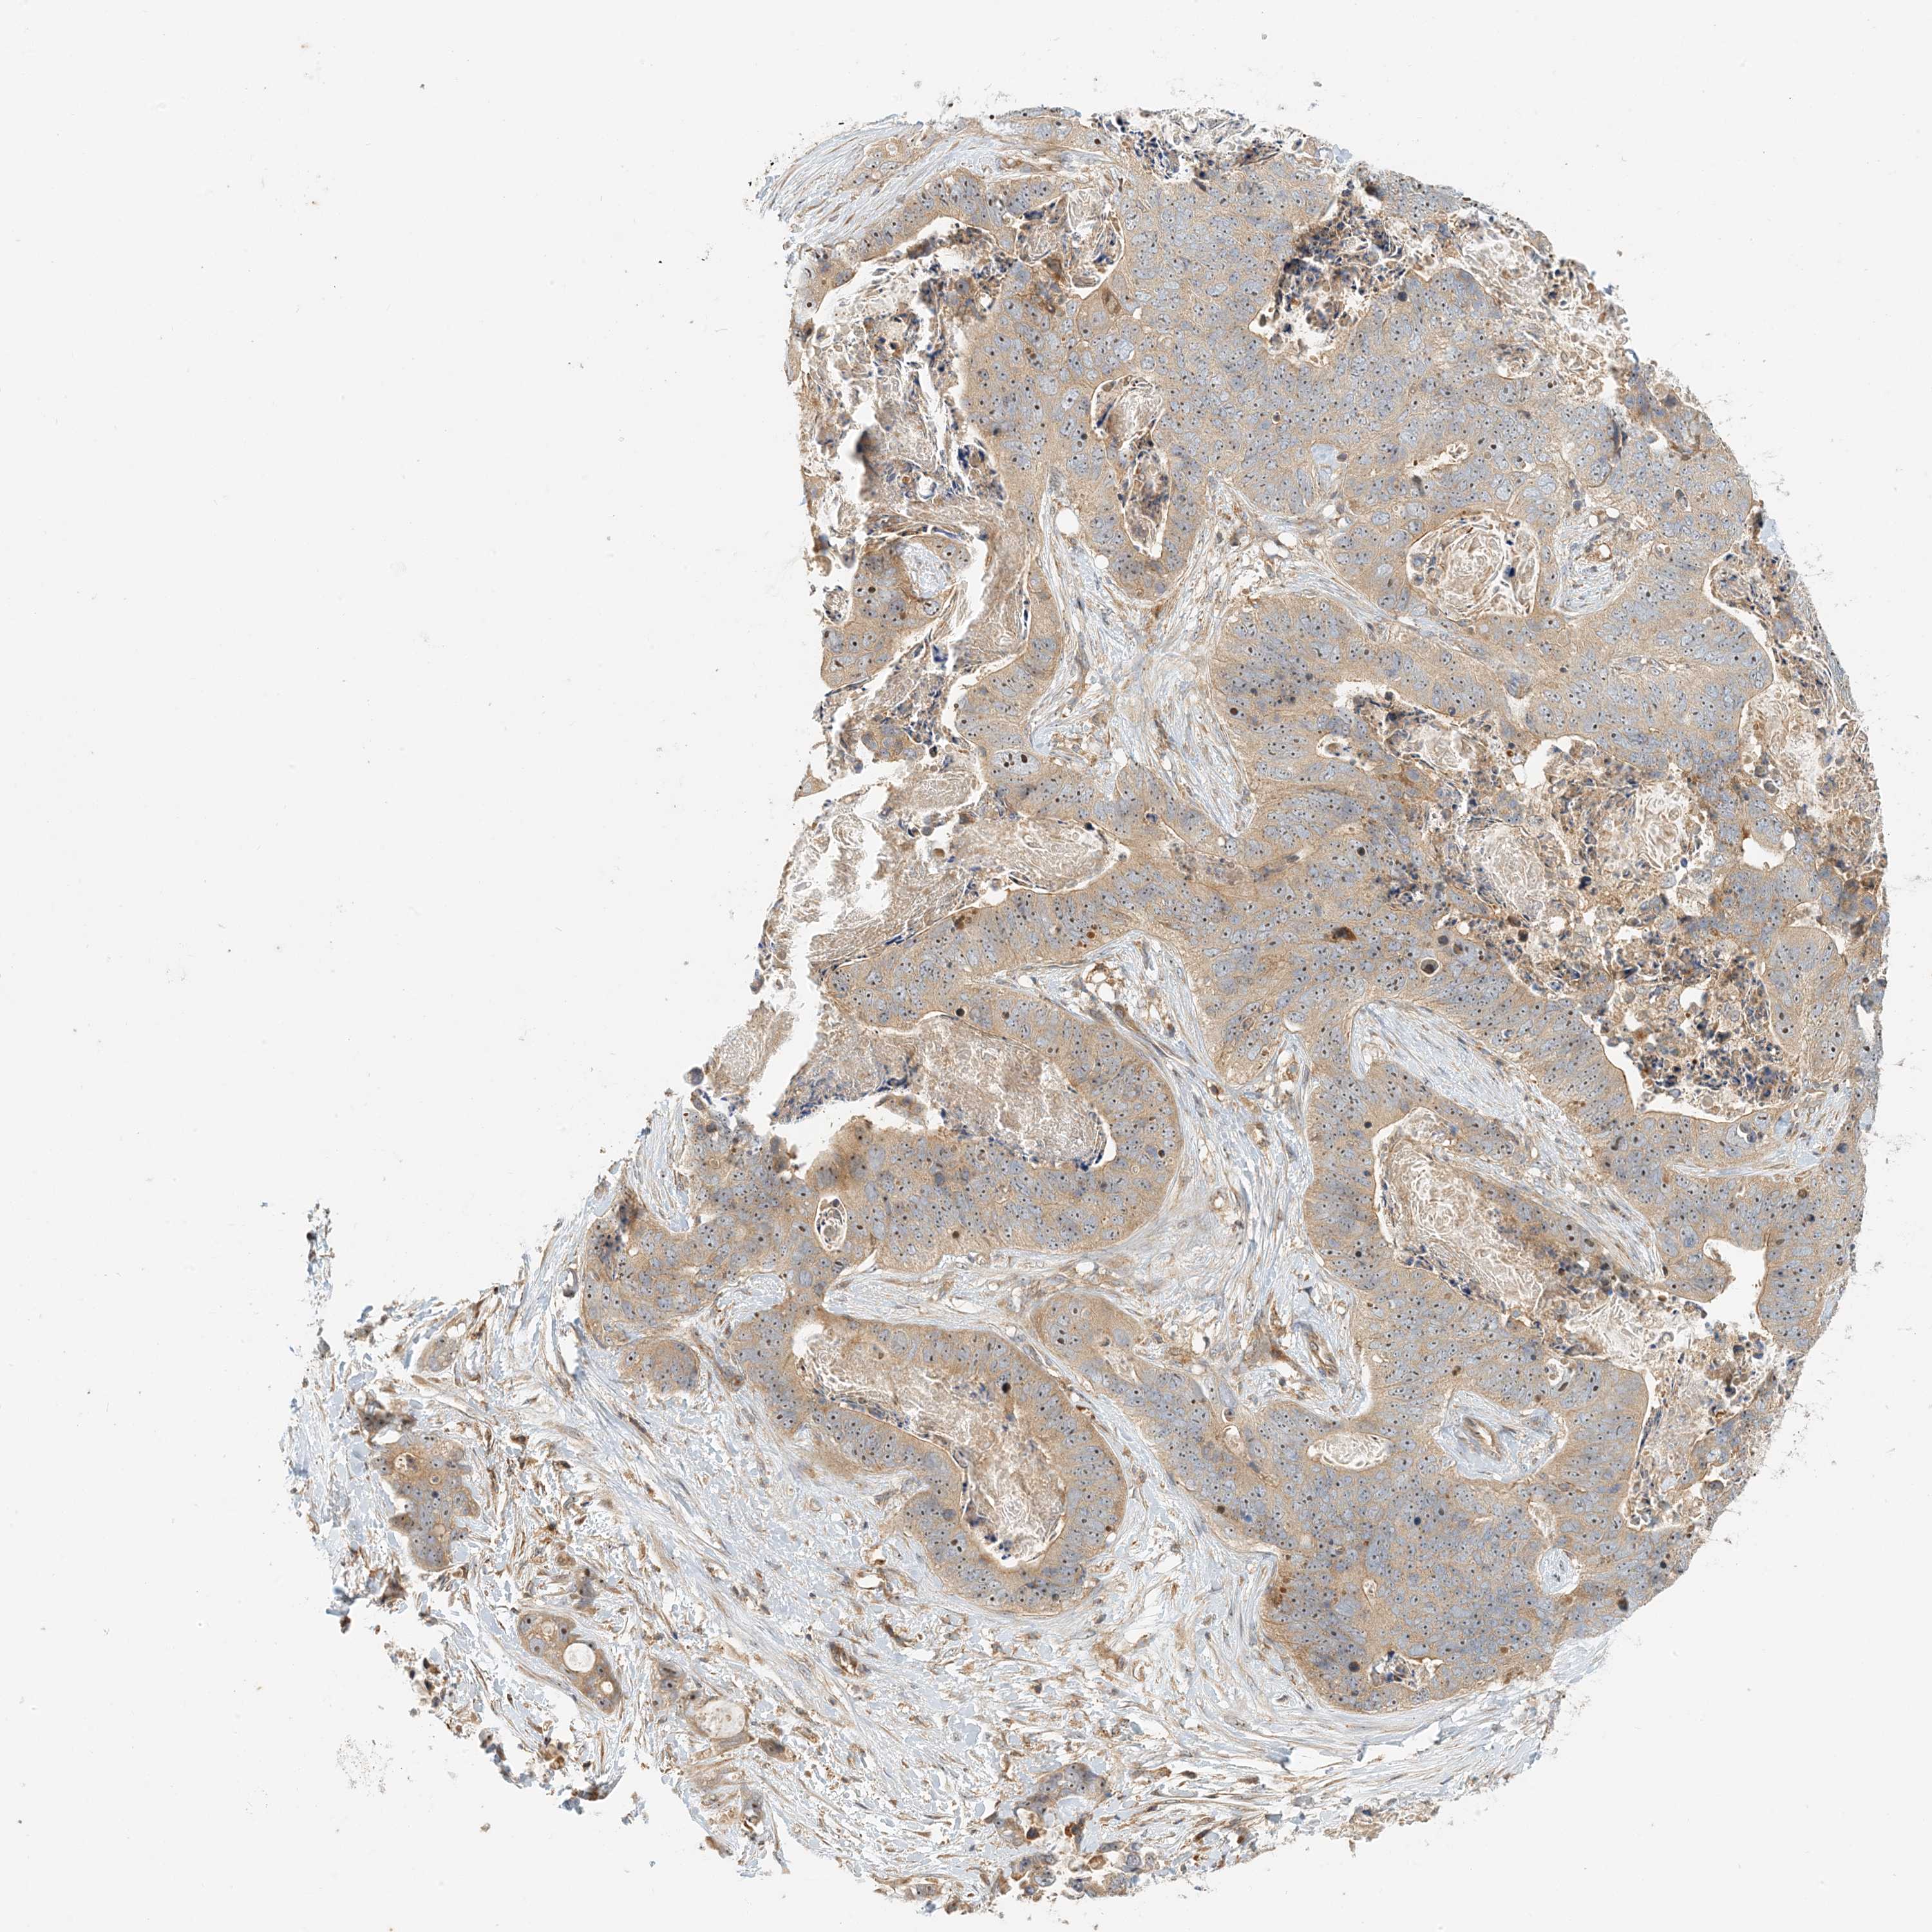

STOMACH CANCER - Protein expressioni

A mouse-over function shows sample information and annotation data. Click on an image to view it in a full screen mode. Samples can be filtered based on level of antibody staining by selecting one or several of the following categories: high, medium, low and not detected. The assay and annotation is described here.

Antibody stainingi

Antibody staining in the annotated cell types in the current human tissue is reported as not detected, low, medium, or high, based on conventional immunohistochemistry profiling in selected tissues. This score is based on the combination of the staining intensity and fraction of stained cells.

Each image is clickable and will lead to virtual microscopy that enables deeper exploration of all samples and also displays staining intensity scores, fraction scores and subcellular localization as well as patient and tissue information for each sample.

Antibody HPA035241

Staining

High

Medium

Low

Not detected

Intensity

Strong

Moderate

Weak

Negative

Quantity

>75%

75%-25%

<25%

None

Location

Nuclear

Cytoplasmic/membranous

Cytoplasmic/membranous,nuclear

Adenocarcinoma, NOS